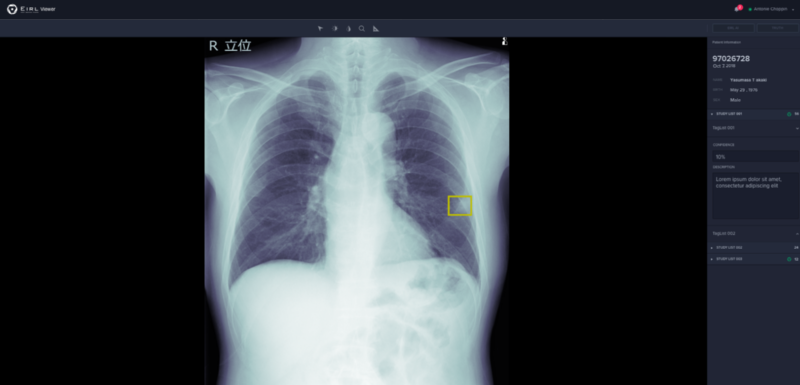

J Mid Eirl エイル Ai画像診断支援技術 エルピクセル株式会社

胸部x線画像から肺結節候補域を検出するaiを開発 プログラム医療機器として承認 エルピクセル Med It Tech

Eirl エイル Ai画像診断支援技術 エルピクセル株式会社 Eirl エイル は Ct Mri 病理画像などの医療画像を中心に多様な医療ビックデータを活用し 独自の人工知能 Ai アルゴリズムで医療画像診断支援技術を研究開発しています 医療機器としての承認をめざし

日本企業の画像診断支援ai開発 18 エルピクセル Imacel Academy 人工知能 画像解析の技術応用に向けて エルピクセル株式会社

日本企業の画像診断支援ai開発 18 診断支援aiプラットフォーム Imacel Academy 人工知能 画像解析の技術応用に向けて エルピクセル株式会社